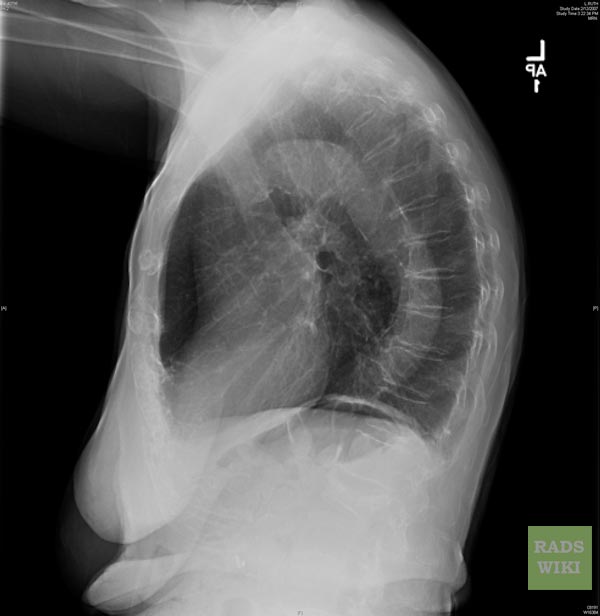

Air Space Disease. Details: Air space disease: The term airspace disease is generally used to indicate a problem involving the alveoli or air sacs in the lungs. Air space lung disease is an unofficial term that refers to air caught in the space between the outside of the lung and the inside of the chest cavity, between the pleural layers that are normally air tight. air space disease.hmmmm.

The purpose of this unit is to demonstrate the appearance of air space disease in the lungs.

The pulmonary acinus is the basic structural unit of the lung involved in gas exchange. Emphysema is the disease in which the air sacs in your lungs collapse. When you think of the causes of consolidation Honeycombing is defined by the presence of small cystic spaces with irregularly thickened walls.